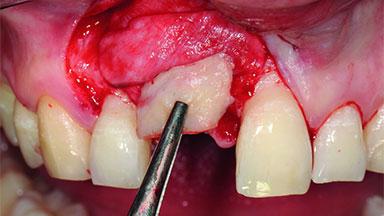

Replacement of a Compromised Upper Right Central Incisor: Hard- and Soft-tissue Augmentation, Late Placement of an RC Bone Level Implant

A 36-year-old male patient with a compromised maxillary central incisor was referred by his general dentist for consultation. The patient’s chief complaints were the gradual debonding of a temporary crown on the right central incisor and unsatisfactory esthetics due to an increasing diastema between the right central and lateral incisors. The patient reported a traumatic event some years previously, when a crown had been placed after root-canal treatment. The referring dentist wanted to provide a new crown restoration, but was concerned about the condition of the residual root. Anamnesis was negative for any other dental or periodontal pathology in the remaining dentition. The patient reported taking no medications: He was a smoker (10 to 15 cigs/day) and had realistic esthetic expectations.

Bone Augmentation Horizontal|Simultaneous|Staged

Augmentation Materials Xenogenous|Membrane

Bone Volume Deficient horizontally, requiring prior grafting